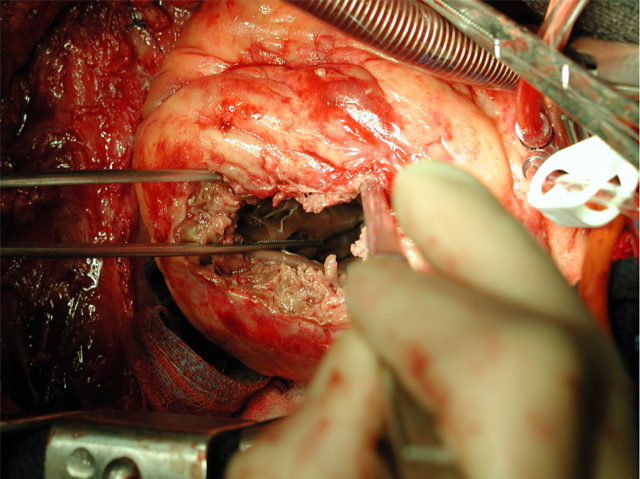

This completes closure of the left ventricular chamber excluding the defect and infarcted septum and ventriculotomy from the high pressures generated by the left ventricle (Figure 7 and 8). It very important that the patch be very floppy and redundant so that it is pushed up against and buttressed by the septum during systole. If the patch is too taut excessive tension will be placed on the sutures and they will rip out.

Excess patch is trimmed off and the ventriculotomy is closed using Teflon strips sewn onto the ventricular wall using interrupted full thickness horizontal mattress sutures of 3-0 polypropylene (Figure 9).

The sutures are then tied, closing the ventriculotomy (Figure 10). This first row of sutures reapproximates the muscle and secures the Teflon to it. As second double running layer baseball stitch is placed incorporating the Teflon strips and upper muscle layers to provide strain relief and seal gaps. This suture line rarely bleed because it is subject to low right sided pressures rather than high left sided pressures.